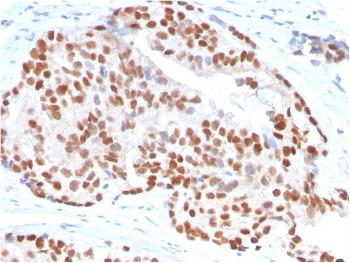

Figure 1: Anti-Involucrin antibody(39-1063). IHC(P): Human Lung Cancer Tissue.

Western blot : 2μg/ml; Immunohistochemistry(Paraffin-embedded Section) : 0.4-1μg/ml; Immunohistochemistry(Frozen Section) : 0.4-1μg/ml; Immunocytochemistry : 1μg/ml